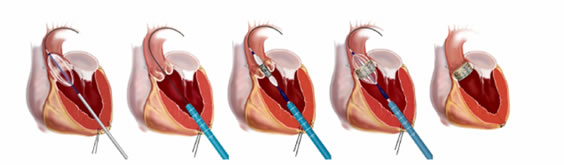

Astfel, s-a imaginat o procedură de implantare valvulară aortică transcateter (TAVI/TAVR) prin care în interiorul valvei îngustate a pacientului se introduce un balon de dimensiuni adecvate cu care valva îngustată este, mai întâi, dilatată sub control radiologic și ecografic transesofagian (fig. 2).

Apoi se introduce pe cale endovasculară, până la nivelul valvei predilatate, o proteză valvulară strânsă în interiorul unei teci. (fig. 3). Proteza valvulară biologică este constituită din ţesuturi de origine animală.

Prin retragerea controlată a tecii, valva se autoexpandează deoarece este inserată pe un schelet metalic de nitiol (fig. 4). Proteza conţine în interiorul scheletului metalic o valvă sintetică nouă, asemănătoare ca structură și funcţie cu cea sănătoasă.

În final, funcţia valvei proprii a pacientului, care rămâne la locul ei fără a fi excizată, este preluată de proteza autoexpandabilă (fig. 5).